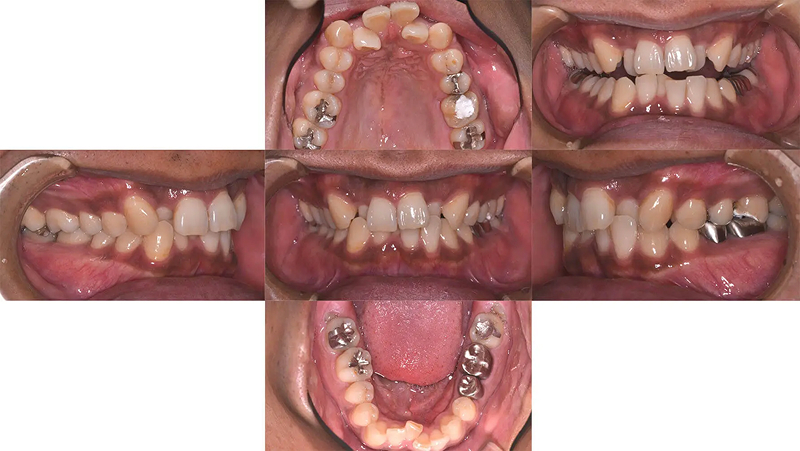

Case02前歯の凸凹を改善した症例

前歯の凸凹が著しい状態でした。清掃がしにくく、上顎側切歯がロックされていました。むし歯治療とともに矯正治療をすることになりました。診査の結果、歯列にスペースがないことがわかりました。口元をきれいにし、歯列を整えるには小臼歯4本抜歯が必要と診断しました。仕事をしながらなので、通院が少し大変でしたが、無事きれいな歯列を獲得できました。

初診 2014.10.16

矯正治療開始 2014.11.26

矯正治療終了 2016.7.12

ファイナル 2016.12.22

治療後2年半 2019.6.24

| 主訴 | 前歯の凸凹を治したい |

|---|---|

| 診断 | 両側アングル1級の叢生 |

| 矯正方法 | 小臼歯4本抜歯を伴うマルチブラケット |

| 矯正期間 | 20か月・21回 |

| 費用 | 746,000円(税別) |

| 調整料 | 月1回 5,000円(税別) |